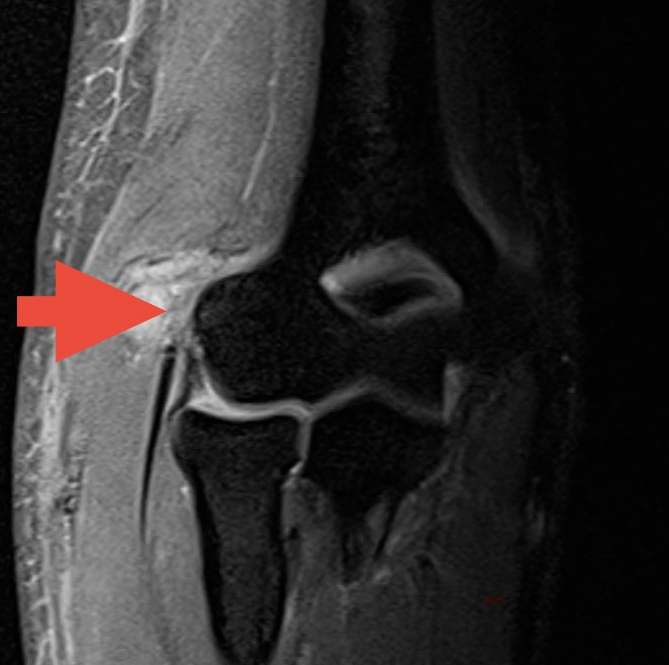

就这样,他被疼痛折磨了两年多,偶尔机会了解到周武忠主任对运动医学疾病的治疗经验丰富,为求进一步治疗,他来到我院找到周主任就诊,结合病史、体查、核磁共振检查,周主任考虑为“顽固性网球肘”,建议通过关节镜微创治疗

微信图片_20250604144937.png

肘关节周围神经血管众多,手术医生要非常有经验,对解剖非常熟悉。术中,周主任在肘关节的两侧,各开了一个仅5mm的微创切口,在镜头的直视下将病灶进行了清理。术后次日,困扰小赵两年多的疼痛明显缓解,“不痛了不痛了!”激动不已。几天后就出院了。目前,小赵的肘关节已经恢复活动自如,再来门诊复查,恢复的不错。